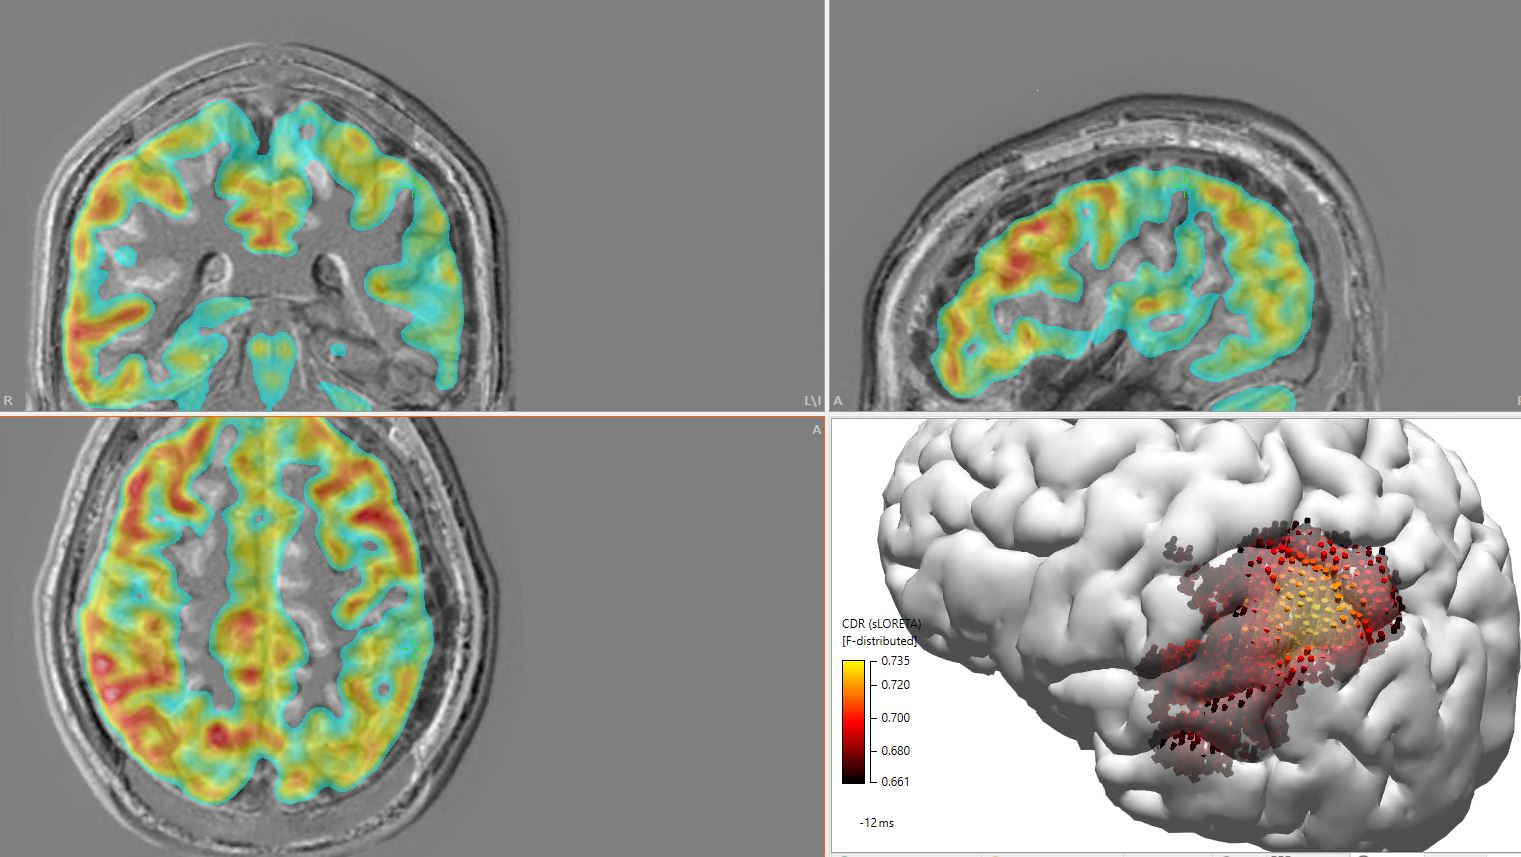

A technologically advanced learning and clinical care environment at USA Health’s state-of-the-art South CEP Epilepsy Monitoring Unit is a primary training location and offers a truly unique experience for our fellows. Clinical rotations include experiences in EEG, such as intracranial Stereo EEG monitoring, bedside and intraoperative mapping, and epilepsy surgical management. Our fellows have the unique opportunity to learn EEG source imaging.